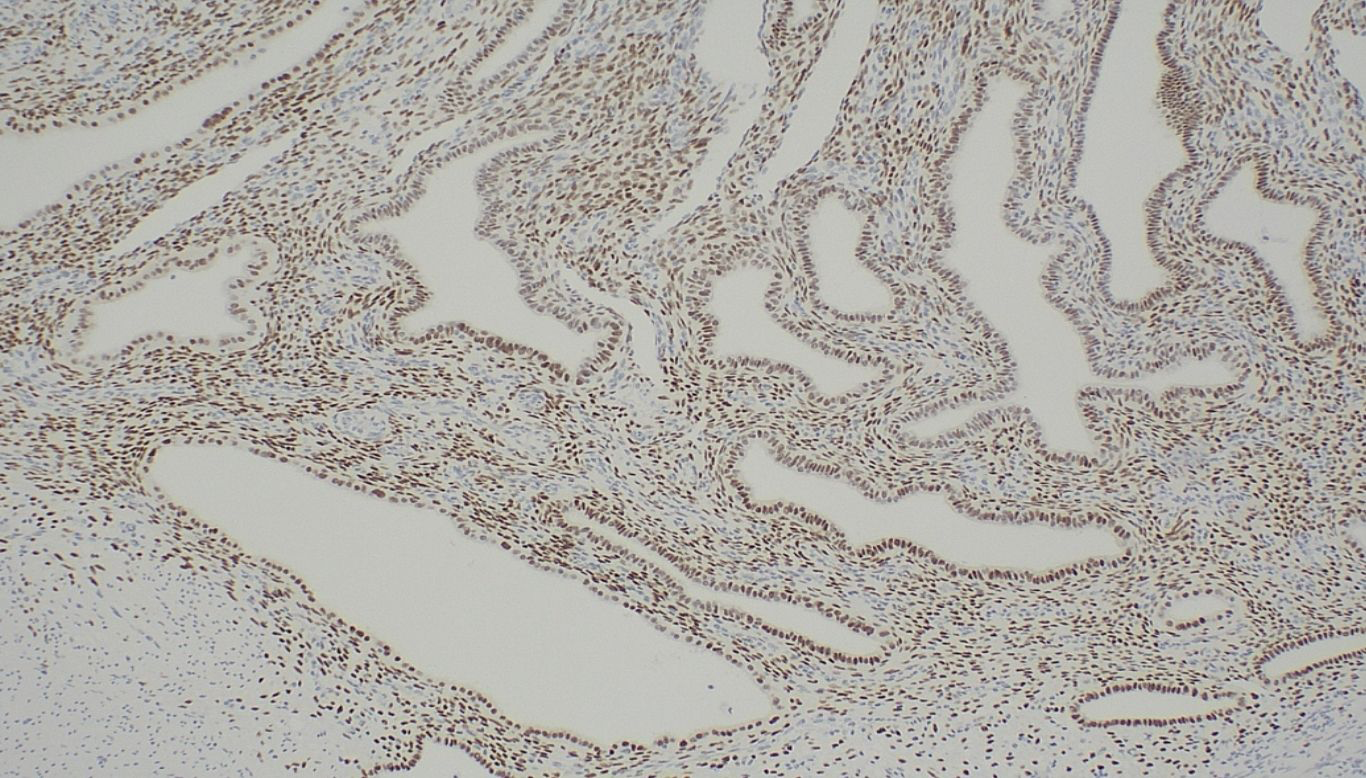

After a multidisciplinary meeting and discussion with the patient, definitive surgical management was recommended in view of the concerns for underlying malignancy. She proceeded to a laparoscopic total proctocolectomy with end ileostomy in early 2024. Histology demonstrated no active colonic inflammation, however the rectal specimens revealed endometriosis of the submucosa and muscularis propria with muscular hypertrophy corresponding to the stricture (Figures 2A, B). Oestrogen receptor immunohistochemistry stained positive in this area, confirming the diagnosis (Figure 3).

Figure 3. Oestrogen receptor immunohistochemistry; positive staining demonstrated within endometrial stroma and glands.